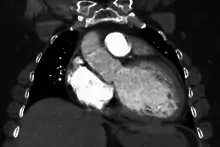

| Mouse heart slice showing dilated cardiomyopathy | |

Generalized enlargement of the heart is seen upon normal chest X-ray. Pleural effusion may also be noticed, which is due to pulmonary venous hypertension.[28]

The electrocardiogram often shows sinus tachycardia or atrial fibrillation, ventricular arrhythmias, left atrial enlargement, and sometimes intraventricular conduction defects and low voltage. When left bundle-branch block (LBBB) is accompanied by right axis deviation (RAD), the rare combination is considered to be highly suggestive of dilated or congestive cardiomyopathy.[29][30] Echocardiogram shows left ventricular dilatation with normal or thinned walls and reduced ejection fraction. Cardiac catheterization and coronary angiography are often performed to exclude ischemic heart disease.[28]

Cardiac magnetic resonance imaging (cardiac MRI) may also provide helpful diagnostic information in patients with dilated cardiomyopathy.[32]